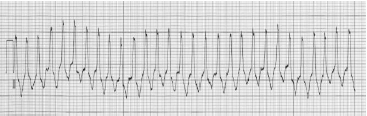

Um paciente é atendido no serviço de emergência após subitamente perder a consciência. Ele encontra-se irresponsivo e sem pulso carotídeo palpável. Após início das manobras de reanimação, o paciente é monitorizado e apresenta o traçado abaixo.

A conduta imediata deve ser